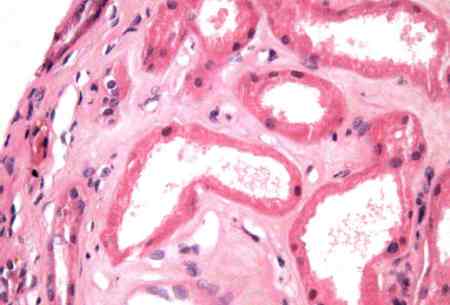

- biópsia renal:

os glomérulos demonstram matriz mesangial aumentada com membranas basais espessadas; depósitos imunes subepiteliais com depósitos subepiteliais e mesangiais ocasionais